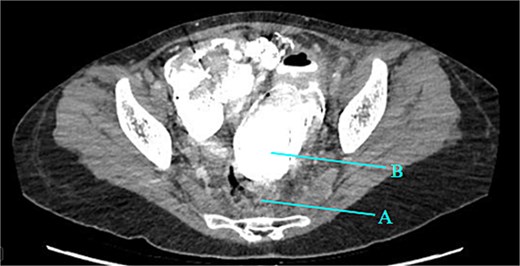

Contrast-enhanced CT of the abdomen and pelvis revealed extensive barium extravasation outlining the peritoneal cavity, accompanied by pneumoperitoneum (Fig. 3). Two barium-outlined, walled-off intra-abdominal collections were identified: one located anterior to the lower pole of the left kidney and the other in the pelvis, anterior to the rectum (Figs 4 and 5). Due to significant barium-related imaging artifacts, the precise site of bowel perforation was not identified. A diagnosis of peritonitis secondary to barium spillage was established, with associated intra-abdominal collections.

Barium-lined intra-abdominal collection (A) anterior to the left kidney (B).